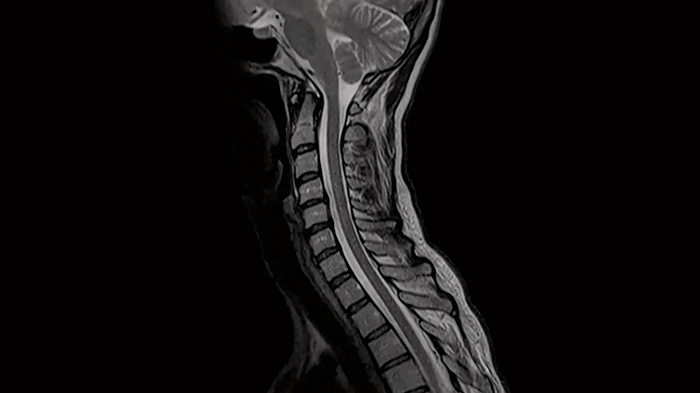

Spine

C-Spine - T2 TSE

Integrate Head/Neck and Spine Coil to gain outstanding C-Spine images with T2 TSE.

• Head/Neck Coil

• Spine Coil

80 cm bore MAGNETOM Free.Max

Image Courtesy: University Hospital Erlangen, Germany | Image-ID: 4aaaa0440